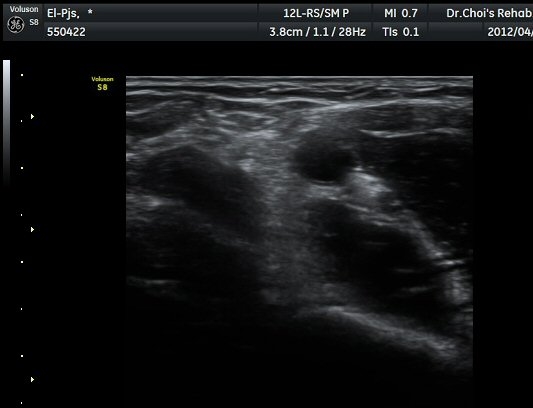

ŽÃËÀÚ¸¦ ÆÈ²ÞÄ¡ ¸»´ÜÀ¸·Î À̵¿ÇÏ´Ï À̵ιڱ٠ÈûÁÙÀÇ ºñÈÄ¿Í ÈûÁÙ ÁÖÀ§¿¡ Àú¿¡ÄÚ ¼ö¾×Àú·ù°¡ ]

°üÂûµÈ´Ù(±×¸² 2, 3, 4, 5). ŽÃËÀÚ¸¦ ¸»´ÜÀ¸·Î À̵¿ÇÒ ¶§ ŽÃËÀÚ¸¦ ¸Ó¸®ÂÊÀ¸·Î °æ»ç(tilting)½ÃÄѾß

À̵ιڱ٠ÈûÁÙ¿¡ Á÷°¢ ÀÇ ÃÊÀ½ÆÄ Á¶»ç°¡ °¡´ÉÇÏ¿© À̵ιڱ٠ÈûÁÙÀÌ °í¿¡ÄÚ·Î °üÂûµÈ´Ù.

À̵ιڱ٠ÈûÁÙ Á¾´Ü¸é°Ë»ç¿¡¼­ ÈûÁÙÀÇ ºñÈİ¡ °üÂûµÇ³ª ÈûÁÙÀÇ ¿ä°ñµ¹±â(radial tuberosity)

ºÎÂøºÎ´Â ºñµî¹æ¼ºÀΰøÀ½¿µ(anisotopic artifact) ¶§¹®¿¡ ¶Ñ·ÈÈ÷ °üÂûµÇÁö ¾Ê´Â´Ù(±×¸² 6).